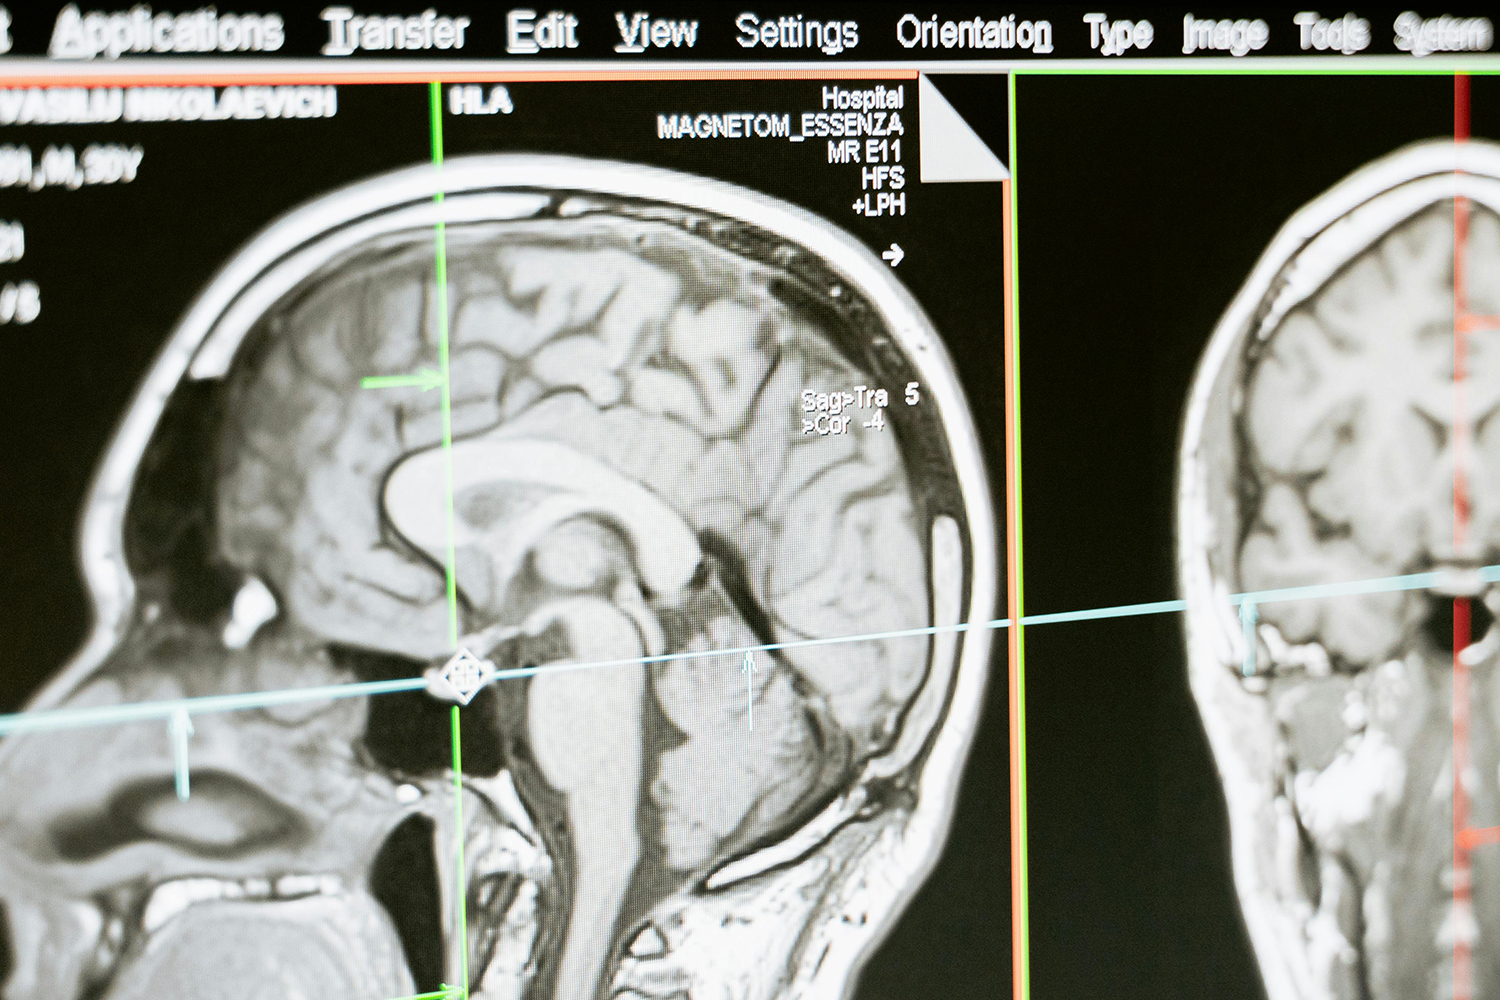

Magnetic resonance imaging (MRI) is now widely used in medical diagnostics due to its non-ionizing nature, making it a safe imaging modality.It offers high flexibility through multi-planar imaging capabilities and supports various contrast mechanisms such as proton density, relaxation, and weighted imaging, along with multiparametric features.As a result, MRI has become one of the most powerful tools in modern clinical diagnosis.However, clinical studies have found that the relaxation times of certain different tissues or tumor types may overlap, making accurate diagnosis challenging in some cases.